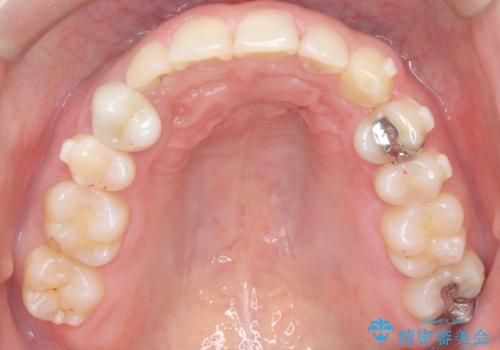

- 下の歯のがたつき(叢生)、真ん中(正中)が右にずれていることを主訴に来院されました。右上前から3番目の永久歯が埋まっている(埋伏)していることから正中は可能な限り合わせることをゴールとしてマウスピースでの矯正治療を選択しました。

今回の矯正治療では、透明なマウスピース型の装置インビザラインを使用しました。がたつきをとるため、安全性が確保できる範囲で歯と歯の間を少し削り必要なスペースを確保しました。